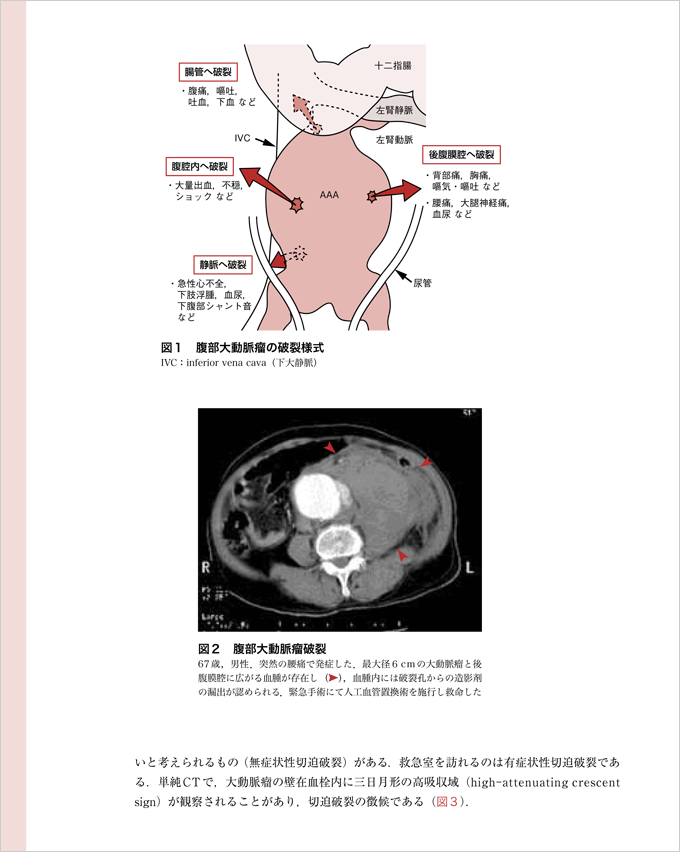

『Lecture9 軽快した腰痛! 失神! 胸部不快! でも…』より抜粋